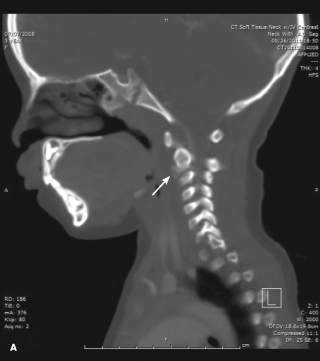

A CT scan of the soft tissues of the neck with contrast showed areas of calcification anterior to the disk space at C2-3 (A, arrow) and at the disk space of T1-2 (B, arrow) with questionable areas of calcification within the disk space at C2-3.